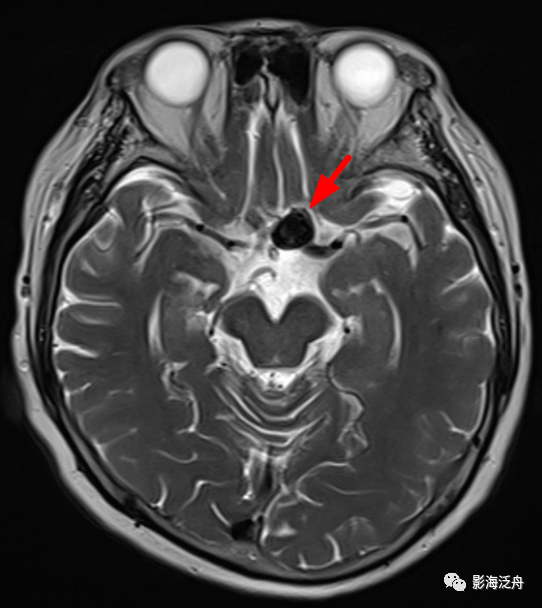

病例二:患者女,78岁,头晕1周,无头痛、恶性呕吐等症状,既往有胃CA手术史和糖尿病、高血压等病史。

病例二:左侧前交通动脉动脉瘤。动脉瘤瘤体显示清晰,呈流空改变,内见斑片状T2WI稍高信号影,可能是湍流造成的。如果脑子里完全没有去观察颅内血管的意识,那就很容易漏诊。